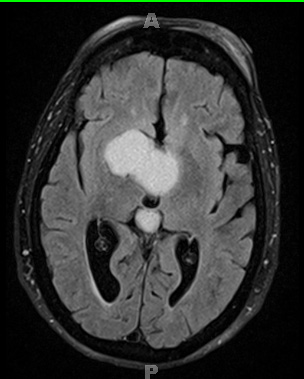

MR imaging performed shows a predominately hyperintense cystic mass in this TIRM Dark Fluid scan.